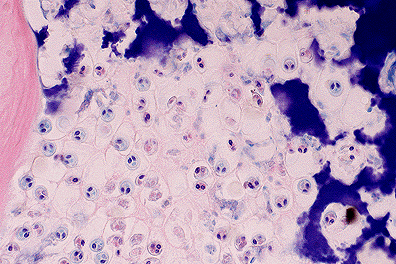

M. cerebralis trophozoites within the cartilage of the head in a rainbow trout. Note the characteristic two prominent polar bodies within each parasite. (40X, HE, 97K)

Laboratory Results: Enzymatic digests performed on head samples showed numerous, approximately 20 æm diameter, acid-fast, spherical spores containing 2 piriform polar bodies and an ovoid sporoplasm, consistent with M. cerebralis.

Contributor's Diagnosis and Comments: Chondritis, granulomatous, multifocal, moderate, chronic, with intralesional myxosporidian trophozoites and spores, consistent with Myxobolus cerebralis.

Granulomatous chondritis with intralesional trophozoites and mature spores are common in juvenile fish infected with M. cerebralis. In older fish, islands of retained, hyperbasophilic cartilage with entrapped spores are within bone; associated inflammation is rare.

The life cycle of M. cerebralis involves a tubificid oligochaete in which numerous motile actinospores (Triactinomyxon gyrosalmo) are produced.2 Actinospores are ingested by trout or directly penetrate the mucous membranes and migrate to bone and cartilage. Asexual reproduction results in numerous trophozoites followed by spore formation within cartilage.3

AFIP Diagnosis: Head, cartilage and bone: Chondritis, granulomatous, multifocal, moderate, with osteitis, perichondritis, and numerous myxosporidian organisms, rainbow trout (Oncorhynchus mykiss), piscine, etiology consistent with Myxobolus cerebralis.

Conference Note: Myxobolus cerebralis utilizes a tubificid worm as an intermediate host. The worm ingests spores of M. cerebralis which then develop into actinosporea in the gut epithelium of the worm. Actinosporea have been shown to infect fish via the water or by ingestion of the worm; presumably the actinosporea penetrate the gut and migrate to cartilaginous tissues where they develop into the spores of M. cerebralis. Although actinosporea have been classified as belonging to the genus Triactinomyxon, it seems that the organisms which comprise this genus may be intermediate forms of myxosporidian parasites. In short, taxonomists have yet to determine how these parasites will be classified.

All species of trout, salmon, and grayling are susceptible to M. cerebralis, the organism responsible for "whirling disease". Clinical signs of whirling disease range from inapparent infection to erratic swimming and death. The abnormal swimming posture and tail-chasing behavior is caused by damage and deformity of the tail and spine secondary to the granulomatous chondritis induced by M. cerebralis. Diagnosis is dependant on demonstrating the protozoa in tissue sections. Identification of the spores may be enhanced by use of Giemsa or acid-fast stains; the spores of M. cerebralis will stain with either.